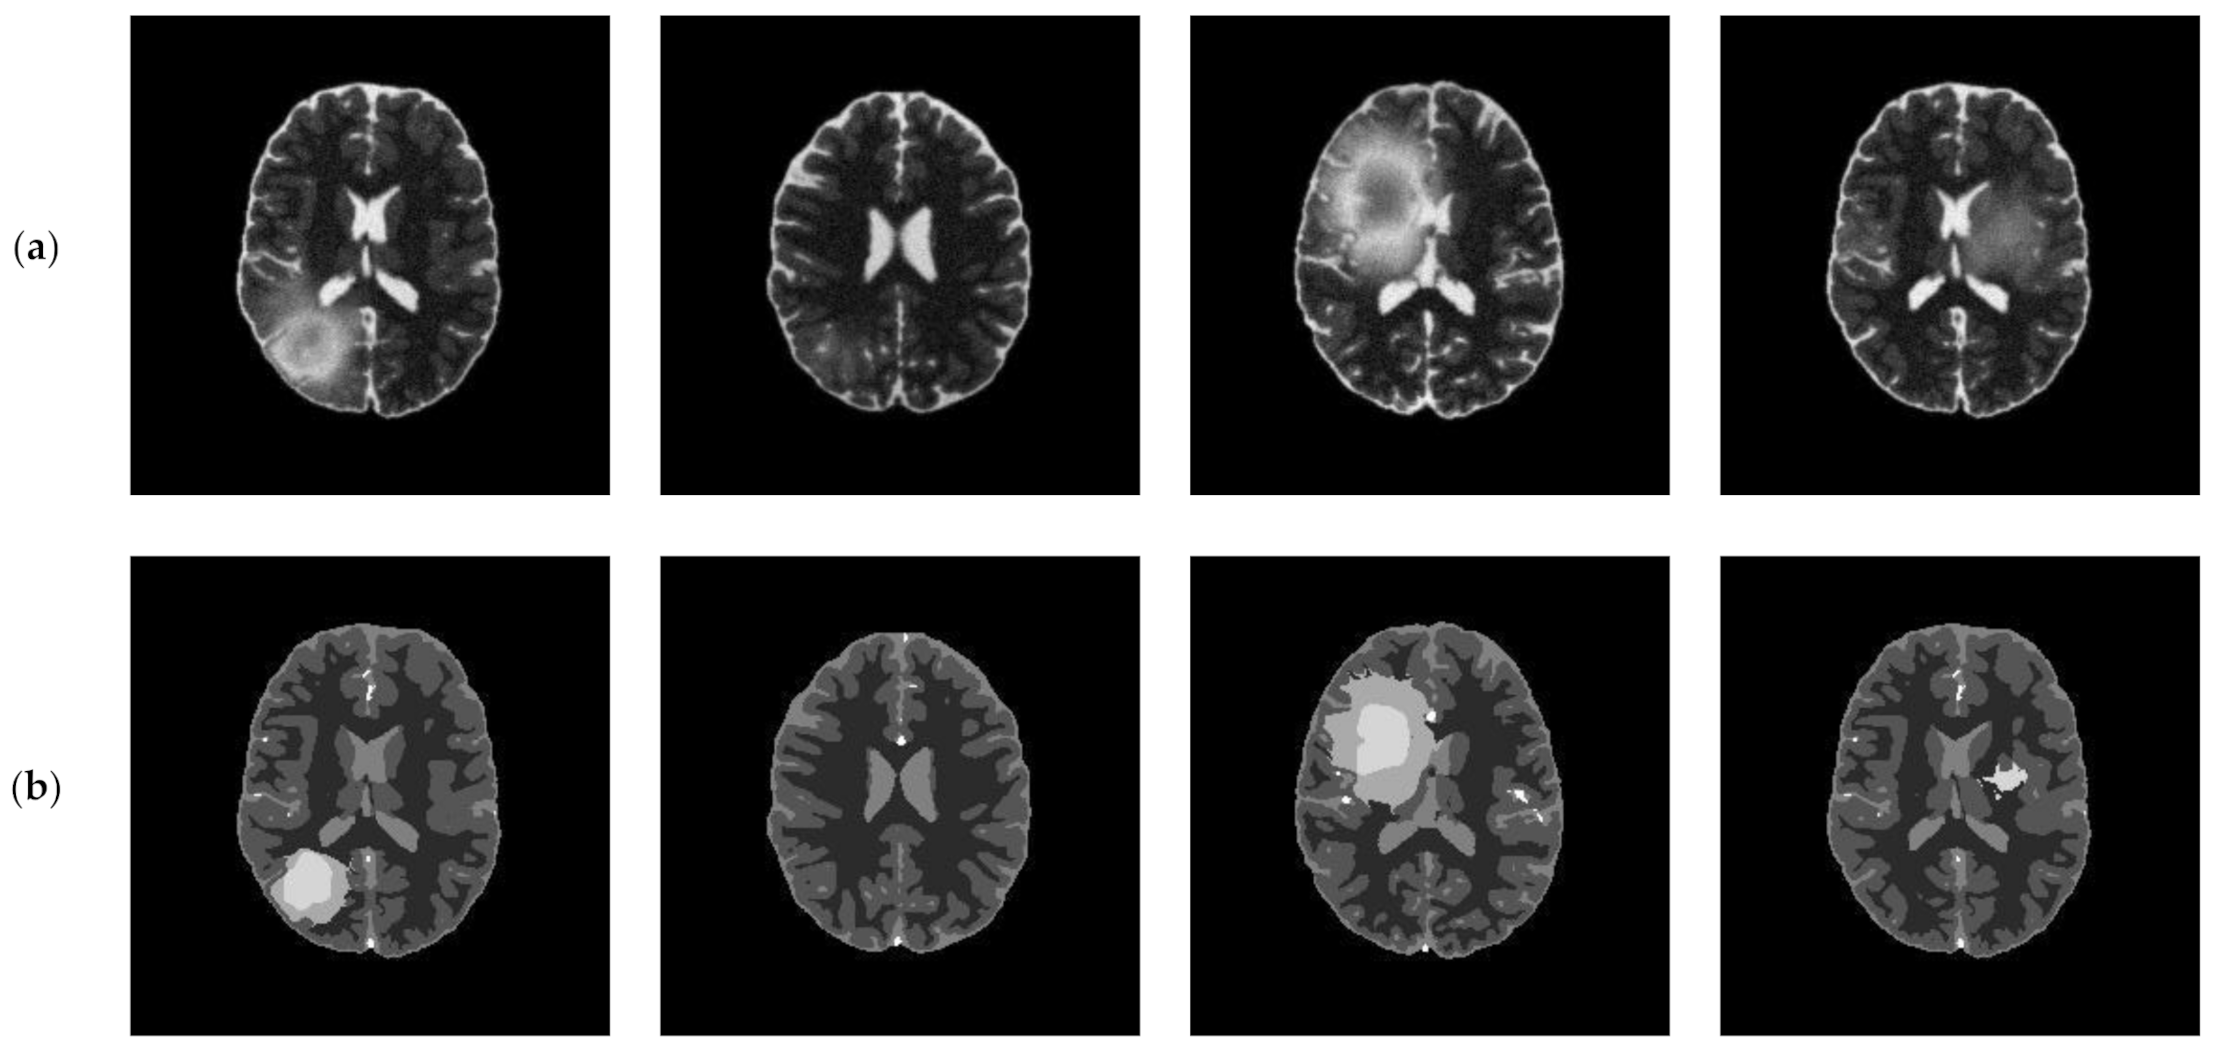

In this subsection, we applied the proposed algorithm to the BRATS (Multimodal Brain Tumor Image Segmentation Benchmark) database. The BRATS database (http://www.imm.dtu.dk/projects/BRATS2012/data.html, accessed on 25 September 2021) is compiled from the international brain tumor segmentation challenge in MICCAI 2012 conference. It is a widely used database and composed of multi-contrast brain MR scans of 25 low-grade and 25 high-grade glioma cases and the corresponding ground truth. Each case includes four modalities—T1, T1c, T2, and FLAIR [44]—and each MR scanning sequence contains more than one hundred images. Figure 20 presents an example of brain MR images from BRATS. Figure 20a shows the original images and the corresponding ground truth is displayed in Figure 20b.

Figure 20.

An example of original images and ground truth from BRATS: (a) original images, (b) ground truth.